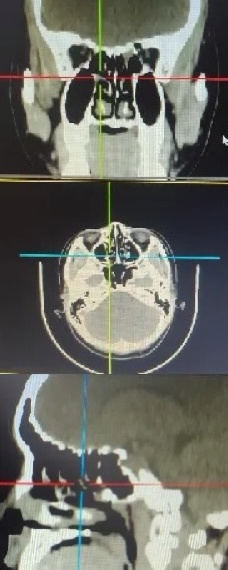

鼻内镜手术

通过鼻内镜进行鼻腔、鼻窦手术,具有创伤小、恢复快的优点。例如:鼻内镜鼻窦手术、鼻中隔偏曲矫正手术、鼻腔肿物切除术等。

鼻窦炎治疗成果展示

治疗前

治疗后